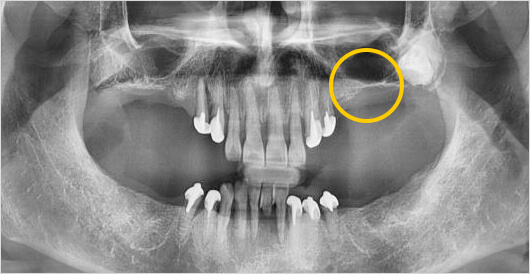

상악동은 코 옆에 있는 두개골의 무게를 줄여주고 숨을 쉴 때

공기 중 노폐물과 코 속의 먼지들을 걸러주는 역할을 하는 빈 공간을 의미합니다.

상악동거상술이란 위 턱 어금니 위쪽에 위치한 상악동을 위로 올려준 후 빈공간에 뼈를 이식하여

임플란트를 식립할 공간을 확보하는 고난이도 수술이기 때문에 충분한 시술경험과 노하우가 있는

병원에서 수술 받으셔야 합니다.

고난이도 임플란트 (상악동 거상술) 수술 전